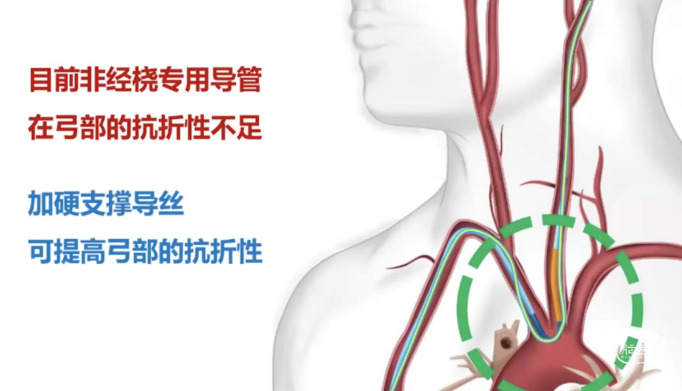

现有中间导管/DA导管相对来说都是经股的设计,尤其是中间导管,一般都是要配合长鞘的外支撑来完成。但是经桡的情况下,它的弓部抗折性其实是不够的。这种情况下,我们需要额外的内部支撑。

导管是否打折,和转弯半径有很大关系。一方面取决于导管性能,一方面取决于血管条件。在没有足够支撑情况下,导管非常容易形成锐角,这个时候就容易打折。目前可以通过加硬导丝增加内支撑,让血管在弯的位置更多地靠在大弯一侧,来增加它的半径,进一步减少打折情况的出现。

如下图病例所示,我们首先用R-DAS技术通过Sim II导管进行降主动脉成形,超选左侧颈总动脉,导丝到位,然后将银蛇DA远端通路导引导管放置到位,其到位后,后面的操作就至关重要,此时使用内部交换技术,将0.035"导丝保留在体内,将造影导管撤出。此时里边仍然有根0.035"导丝,然后再置入一根0.018"的加硬导丝,放置到位。0.018"导丝头端到达银蛇DA远端通路导引导管的头端,这个时候再撤出0.035"导丝,在整个过程中,银蛇DA远端通路导引导管内部一直有一根导丝在支撑,就可以完全避免导管打折。